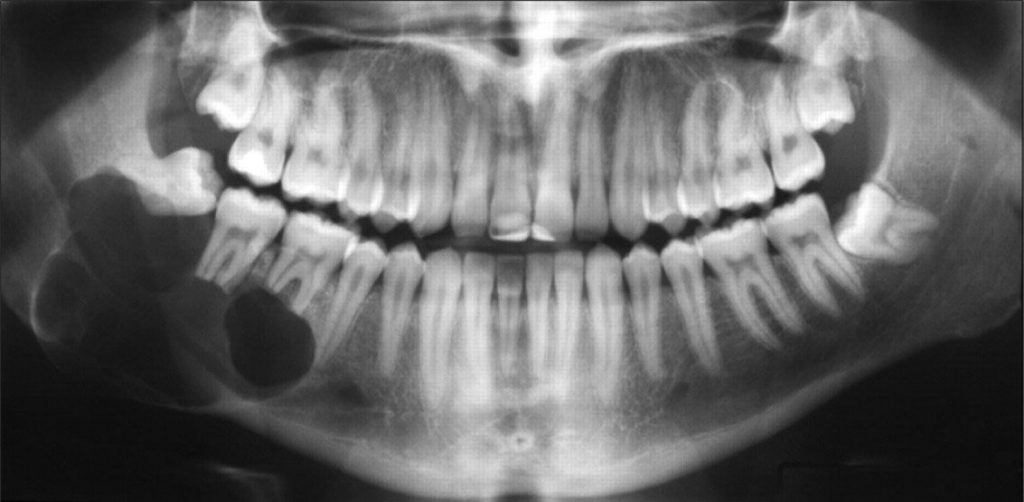

- Nang thân răng: răng khôn mọc ngầm có thể tạo nang thân răng tiến triển âm thầm trong xương hàm. Nếu không được điều trị kịp thời sẽ gặp tình trạng tiêu xương hàm và gia tăng nguy cơ gãy xương hàm.

Hình ảnh bệnh nhân bị nang thân răng